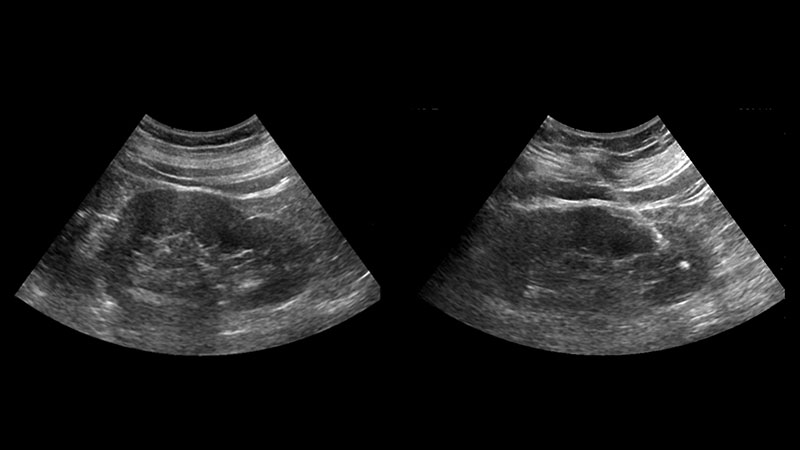

Il Nipt test è uno screening prenatale non invasivo che consente di valutare la possibilità di Trisomia 21 (o Sindrome di Down) e delle trisomie 13 e 18 in un nascituro. Si tratta di un test che fino ad ora «poteva essere eseguito solo privatamente e non era rimborsato dal Servizio sanitario regionale. Il costo si aggirava sui 700 euro», come spiega La Repubblica in un suo articolo.

Ora, invece, con l’aggiornamento del Lea (Livello essenziali di assistenza), gli screening prenatali non invasivi sono stati inseriti nelle prestazioni erogabili dal Servizio Sanitario Nazionale. Basterà un semplice prelievo di sangue e permetterà di «ridurre sempre di più il ricorso ad amniocentesi e villocentesi, che presentano una seppur bassa percentuale di rischio di aborto».